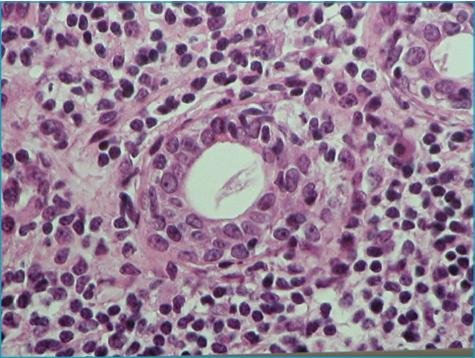

L’association marocaine des maladies auto-immunes et systémiques (AMMAIS) lance un appel aux pouvoirs publics pour que la maladie de Gougerot-Sjögren soit reconnue comme une affection de longue durée.

spécialiste en médecine interne et en gériatrie, a organisé, avec le soutien du laboratoire Sothéma et de la fondation Omar Tazi, une conférence-débats, le samedi 5 mai à Casablanca sur les problèmes de sécheresse des muqueuses et de la peau : le syndrome sec. La réunion des professionnels de la santé et du grand public, lors de cette manifestation, a permis un large échange d’informations sur la prise en charge de ces pathologies et sur les attentes des malades, notamment à l’égard d’une de ses formes les plus pernicieuses, la maladie de Gougerot-Sjögren.

1°)d’améliorer le système de la couverture sociale en reconnaissant la maladie de Gougerot comme une affection de longue durée (ALD), de par son caractère invalidant et chronique (comme la polyarthrite rhumatoïde) ,